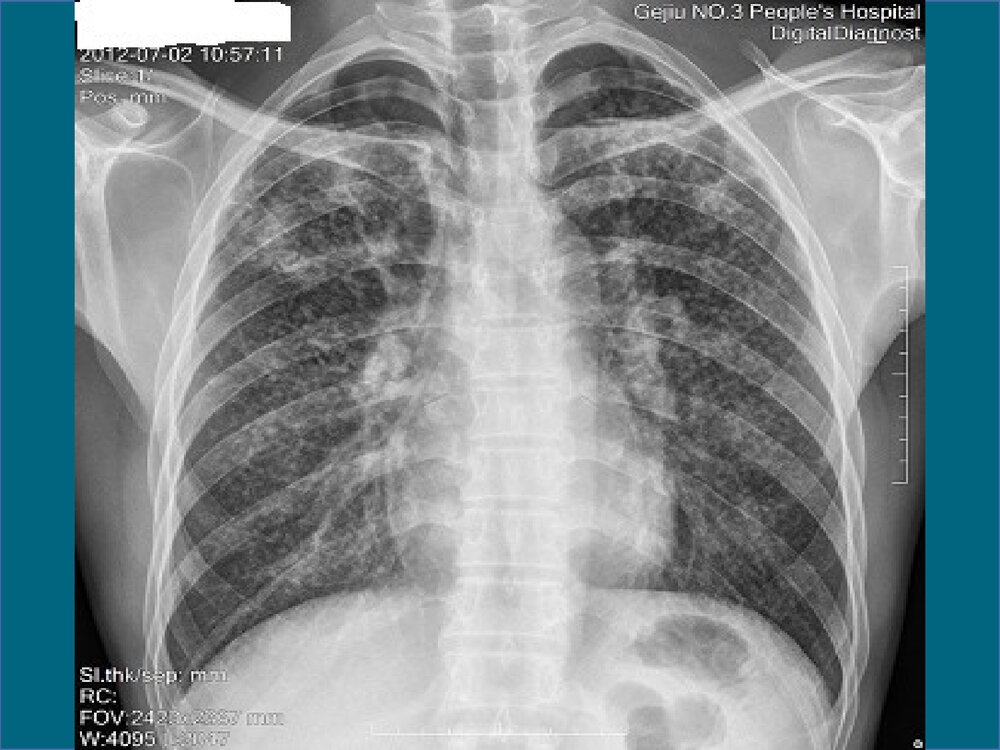

一、生产性粉尘与职业性肺部疾患11、生产性粉尘的基本概念、生产性粉尘的基本概念生产性粉尘是专指在人类生产活动产生的能较长时间悬浮在生产环境中的固体微粒。它是污染生产环境、危害劳动者健康的重要职业病危害因素。根据其化学性质分为⑴无机粉尘,如矽尘,含碳粉尘;⑵有机粉尘等两大类;⑶混合性粉尘等三大类。22、生产性粉尘的来源、生产性粉尘的来源就其产生方式有以下几种:(1)固体物质的机械加工或爆破、破碎、磨粉等。(2)物质加热时产生的蒸气在空气中凝结或被氧化所形成的尘粒,如金属熔炼,焊接、浇铸等。(3)有机物质不完全燃烧所形成的微粒,如煤类等燃烧时所产生的烟尘等。水泥制造业:从生料煅烧、熟料冷却、熟料粉磨、水泥包装、水泥均化、水泥煤粉制备、水泥输送都有粉尘产生。33、...